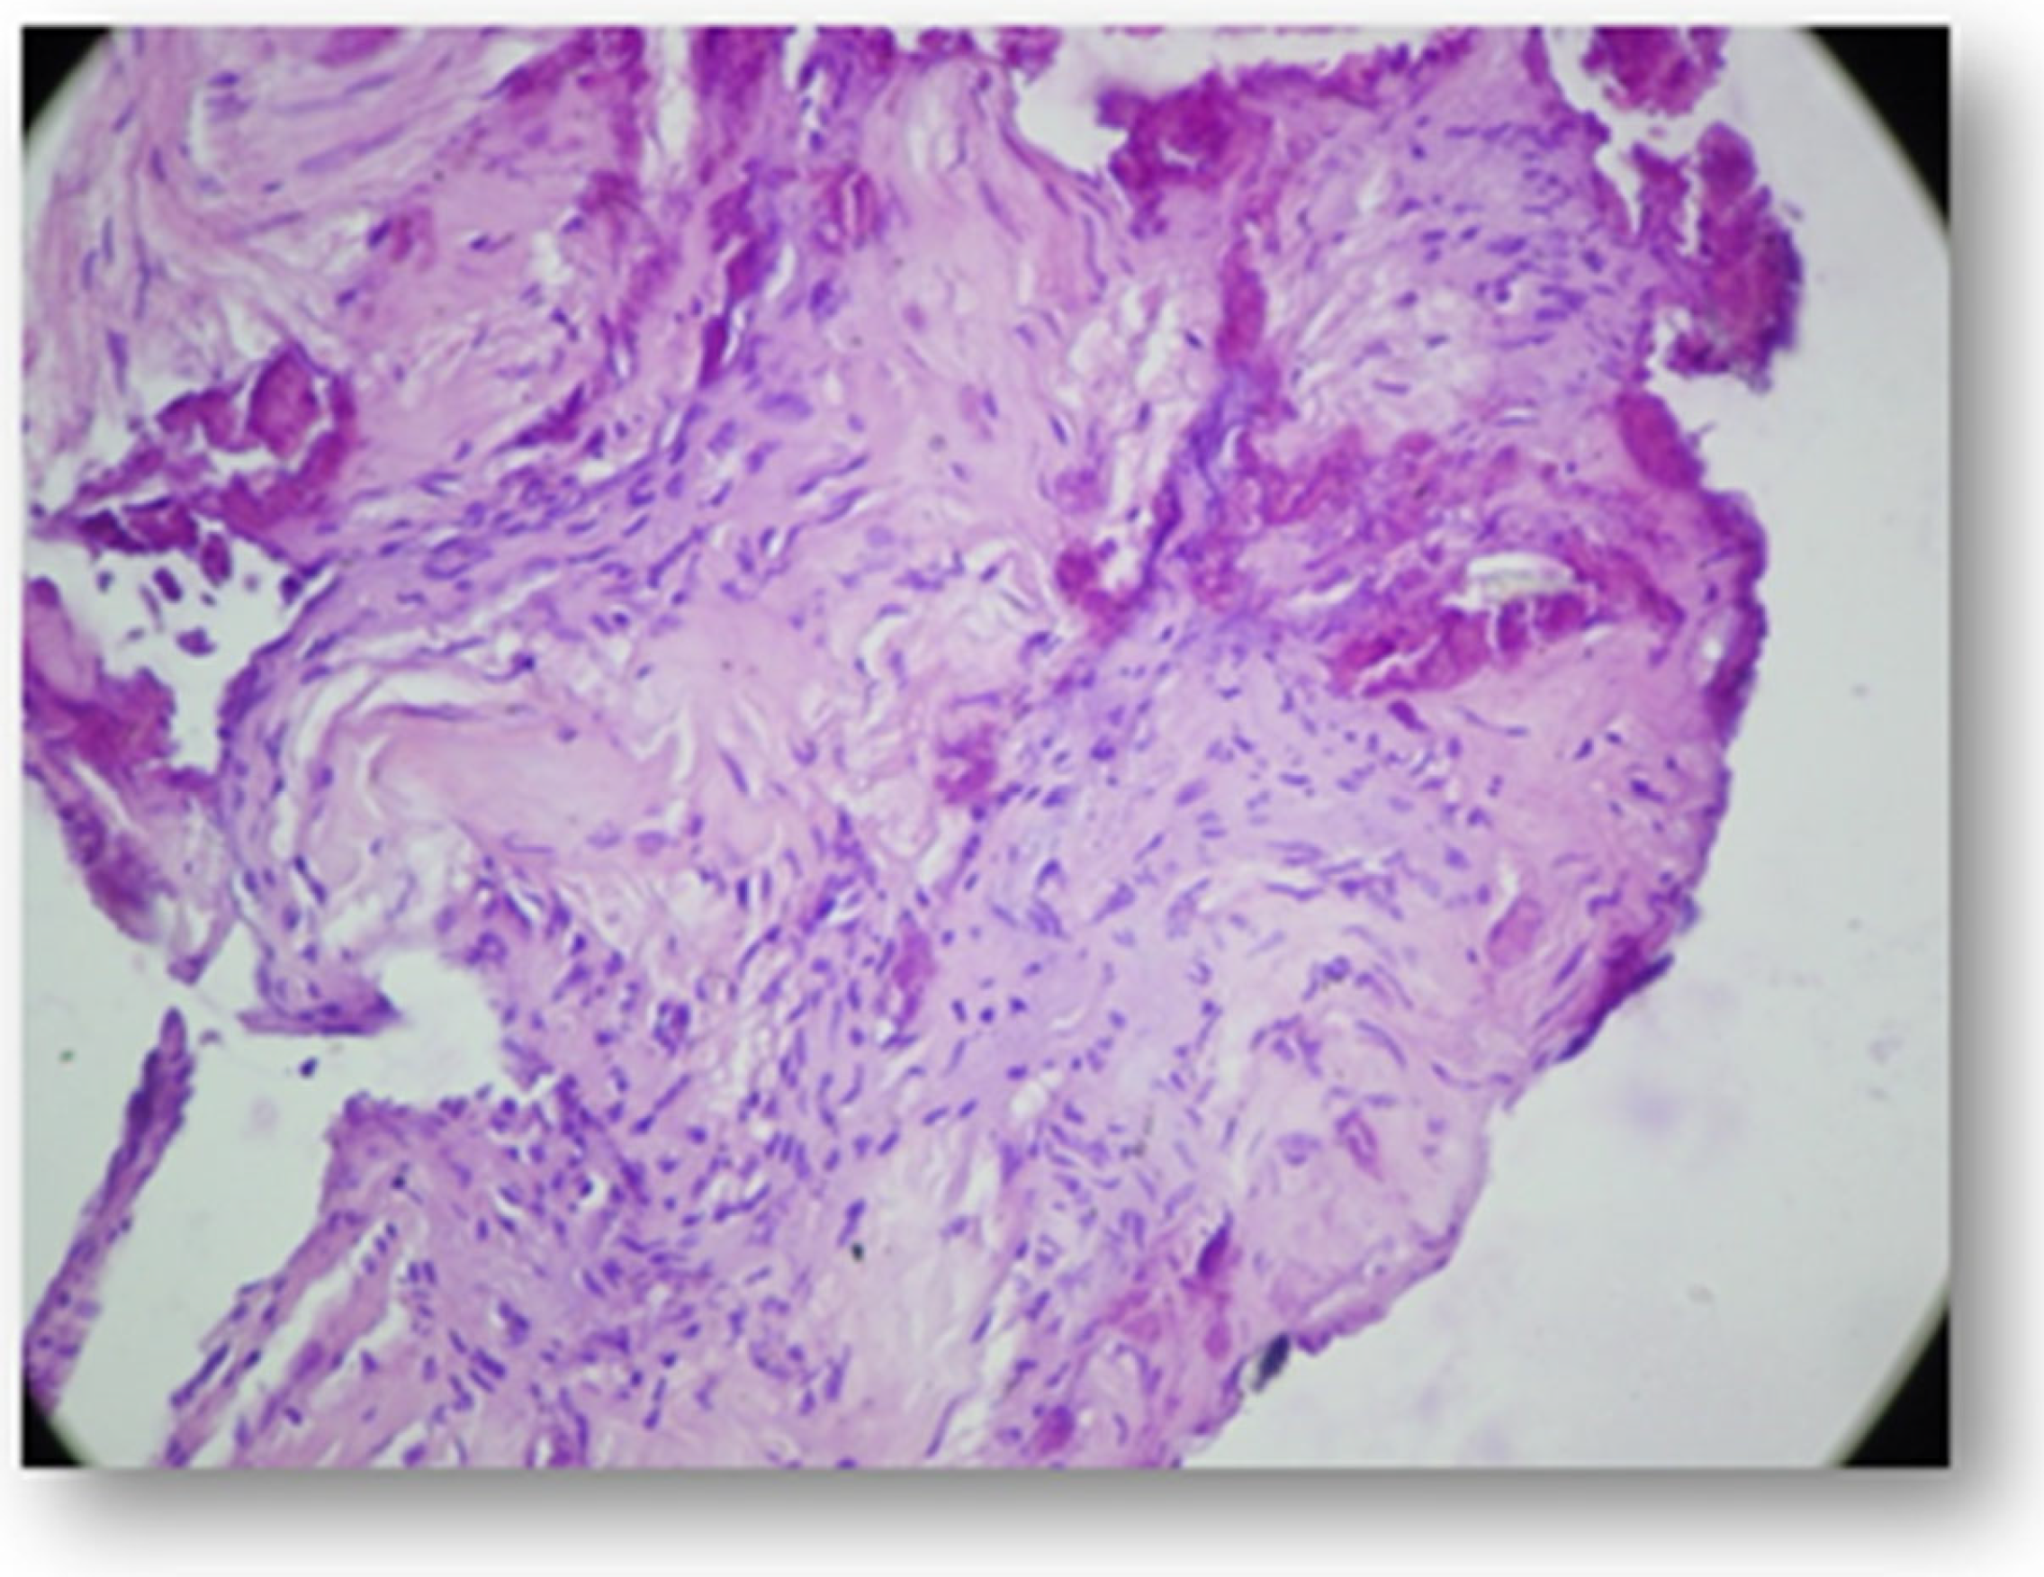

- Moraru, A.I.; Gheorghiţă, L.M.; Dascălu, I.T.; Bătăiosu, M.; Manolea, H.O.; Forna, D.A.; Râcă, A.M.; Raţiu, C.A.; Diaconu, O.A. Histological and immunohistochemical study on the dental pulp of patients with diabetes mellitus. Rom. J. Morphol. Embryol. = Rev. Roum. Morphol. Embryol. 2017, 58, 493–499. [Google Scholar]

- Shetty, P.; Mulay, S.; Singh, M.; Singh, M.; Reddy, M.; Chawla, M.; Shaikh, M. Histological changes in dental pulp of diabetes mellitus (type II). Int. J. Curr. Res. 2017, 9, 57815–57818. [Google Scholar]